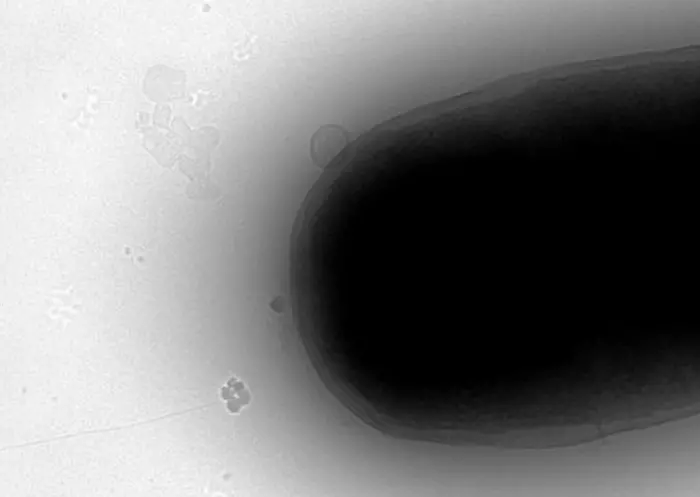

Scientists from Australia and the United States have found a new way to alter the DNA of bacterial cells – a process used to make many vital medicines including insulin – much more efficiently than standard industry techniques.

Instead of opening bacteria cell walls with harsh chemicals or high temperatures to insert DNA, the team used high-frequency radio waves, a much gentler approach that led to many more of the cells taking on the DNA and surviving.

The study, led by RMIT University in collaboration with other Australian universities and WaveCyte Biotechnologies in the US, used radio waves at the 18 gigahertz frequency to temporarily ‘open the gates’ in E. coli bacterial cell walls long enough for genetic material to be inserted.

The team’s results showed the process to be highly efficient: 91% of the E. coli cells took on the new DNA after exposure to 18GHz radio waves for three minutes.